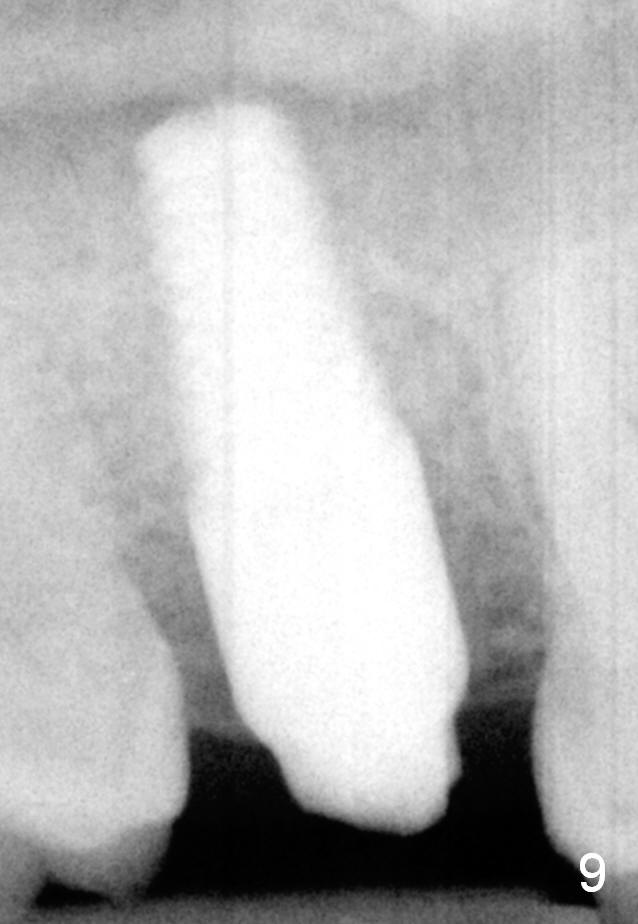

A 42-year-old man is afraid of dentistry. Residual roots of #2 remain untreated for at least 2.5 years (Fig.1). Both the mesiodistal space and the height are limited and unfavorable to restoration (Fig.2,3). Finally he agrees to have treatment, since the tooth #15 is worn so much that it is sensitive to mastication. When the tooth #2 is extracted, the socket is triangular without septum (Fig.4); the bottom of the socket is flat and easy for osteotomy. A 5x17 mm tap has obtained stability once it is placed ~ 14 mm deep (Fig.5). A 5x14 mm implant is placed with insertion torque > 60 Ncm (Fig.6 I), followed by placement of 4x3 mm abutment (A).

To prevent the narrow spaces from getting worse during osteointegration, an immediate provisional is to be fabricated. There is not enough occlusal clearance when the abutment is reduced ~1.5 mm. The abutment is removed; the implant is placed ~ 1 mm deeper with primary stability. Then the occlusal clearance is sufficient; the provisional is made. Mixture of autogenous bone, allograft and Osteogen is placed in the remaining buccal and lingual sockets (Fig.7 *). The provisional is temporarily cemented (Fig.8 P), which keeps the bone graft in place.